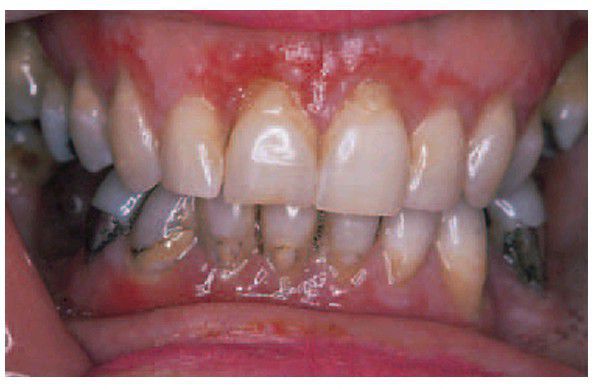

Desquamative gingivitis caused by lichen planus. A well-defi ned band of patchy erythema extends across the full width of the attached gingiva around several teeth. This change may be localised or widespread. Within the red areas faint white fl ecks and striae are sometimes visible